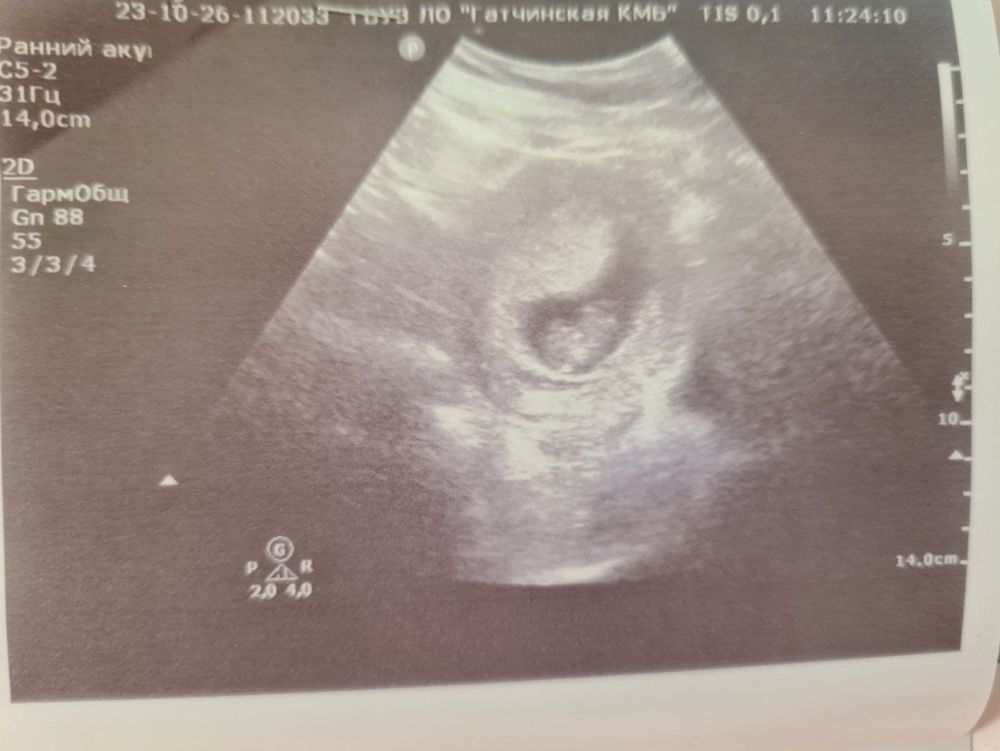

Началась 9 неделя, первый поход на УЗИ, анализы крови

Анализы, скринингиСегодня ровно 9 недель, по этому поводу решили с папой нашей маленькой вселенной сходить на УЗИ. А то все чуть ли не сразу после задержки начинают ходить, а у меня "отчетный период с НДСом, прибылью и вообще, а там разве там хоть что-то видно? О_о", - надо было это срочно исправить))

КТР 24мм, соответствует 9 неделям беременности

ЧСС плода 170 ударов в минуту

Желточный мешок 4мм

Мне, правда, это мало о чем сказало, но раз врач сказал, что все окей, то и хорошо))

На распечатанном снимке, как по мне, вообще ничего не видно, но когда на экране увеличили изображение, и я увидела голову, тельце и пуповинку, то аж зависла: "То есть кроме непонятных пятен на УЗИ можно еще хоть что-то нормально разобрать? Оно правда во мне растет и даже как-то шевелится? О_О Аааа, так вот как зарождение вселенной выглядит))))"